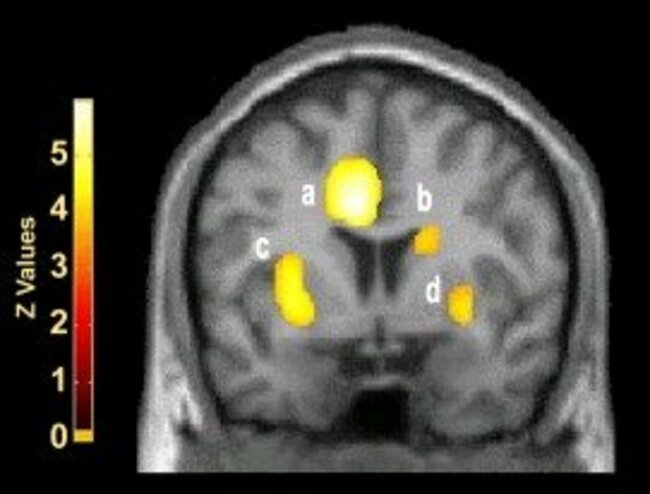

Another study found four brain regions that were specially activated when watching sexually explicit films (and not when watching neutral or comedic films).

The four spots of the brain that activate when watching a sexually explicit film. (Fonteille, et al, Sexologies, 2011)

• The first was the inferior temporal cortex, a region also corresponding to the visual associative zone. The researchers inferred that the subject was assessing and analysing the visual stimulus when this zone was activated, corresponding to the perceptive-cognitive component of sexual arousal.

• The second region was the right orbitofrontal cortex, which might be related to emotional and motivational phenomena.

• The third area was the left anterior cingulate cortex, which appears to control primary physiological responses (endocrine and autonomic), but also affective responses, to sexual stimuli. In other words, it would govern physical and psychological preparation for sexual activity.

• The fourth region was the right insula, that could be involved in subjective perception of physiological modifications associated with arousal (heart rate acceleration, penile erection, etc.)

• Finally, the right caudate nucleus probably controls whether sexual arousal is followed by sexual activity.